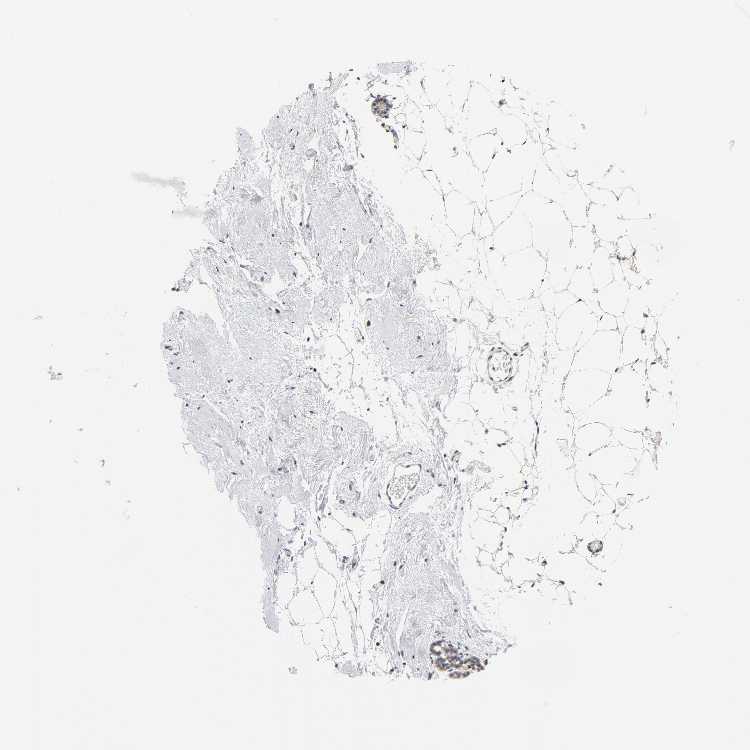

Antibody CAB005195

Adipocytes Not detected

Glandular cells Low

Myoepithelial cells Not detected

BREAST - Antibody stainingi

Antibody staining in the annotated cell types in the current human tissue is reported as not detected, low, medium, or high, based on conventional immunohistochemistry profiling in selected tissues. This score is based on the combination of the staining intensity and fraction of stained cells.

Each image is clickable and will lead to virtual microscopy that enables deeper exploration of all samples and also displays staining intensity scores, fraction scores and subcellular localization as well as patient and tissue information for each sample.